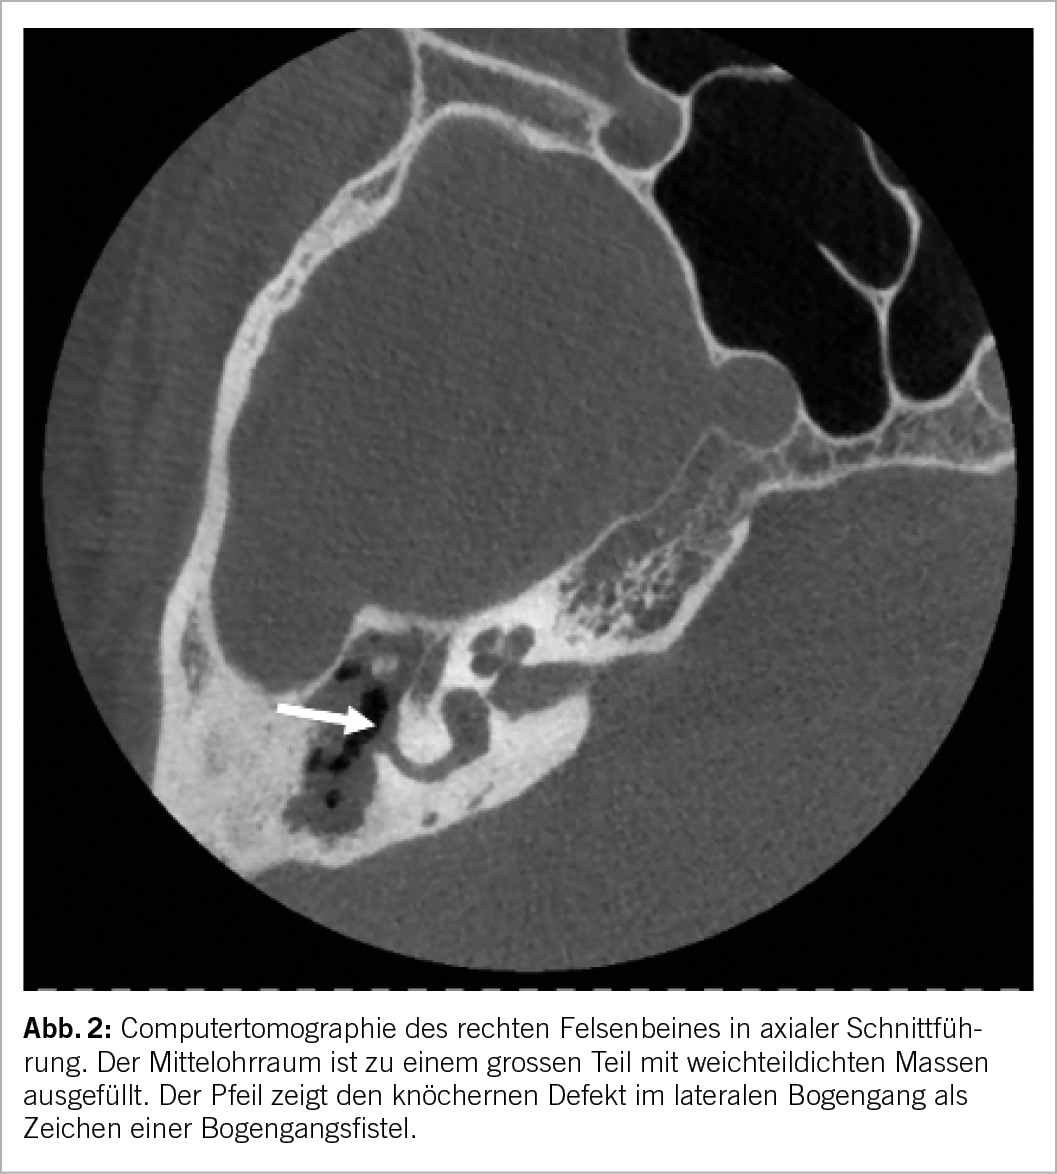

Richtig ist C. Eine Bogengangsfistel ist eine klassische Komplikation eines Cholesteatoms. Ihre korrekte Vermutung wird in einem

Felsenbein-CT bestätigt (Abb. 2).

Bei unserem Patienten liegt ein Cholesteatom vor, also eine Unterform der chronischen Otitis media. Die chronische Otitis media wird durch eine persistierende Trommelfellperforation definiert und in zwei Formen eingeteilt. Die chronische Otitis media simplex äussert sich mit einer sogenannten zentralen Trommelfellperforation. Zentral bedeutet hier, dass um die Perforation herum immer noch ein kleiner Saum Trommelfell bestehen bleibt. Im Kontrast dazu weist die chronische Otitis media cholesteatomatosa typischerweise eine randständige Trommelfellperforation auf. Die Perforation reicht hier also über die Begrenzung des Trommelfells hinaus bis in die Gehörgangshaut hinein. Beim Cholesteatom wächst Plattenepithel ins Mittelohr ein, wo sich normalerweise Schleimhaut befindet. Im Cholesteatomsack wird dabei Keratin retiniert. Dies löst einen chronisch-entzündlichen Prozess mit Osteolyse aus. Leitsymptom ist neben der schleichenden Schwerhörigkeit häufig die fötide Otorrhoe. Neben der Schwerhörigkeit durch die Destruktion der Gehörknöchelchen ist die Bogengangsfistel mit der Gefahr einer Ertaubung eine häufige Komplikation eines unbehandelten Cholesteatoms, seltener eine otogene Meningitis oder eine Fazialisparese. Therapie der Wahl stellt in der Regel die operative Entfernung des Cholesteatoms dar. Eine medikamentöse Therapie ist nicht möglich. Einzig akute Entzündungschübe, welche sich als fötide Otorrhö äussern und in der Regel durch Pseudomonas-Infekte ausgelöst werden, können symptomatisch mit antibiotischen Ohrentropfen beruhigt werden. Bei der operativen Therapie wird als wichtigstes Ziel das Cholesteatom radikal entfernt, gleichzeitig auch eine Hörrehabilitation durch eine Ossikuloplastik mit mikrochirurgischer Rekonstruktion der Schalleitungskette oder Einsatz eines Mittelohrimplantates durchgeführt.